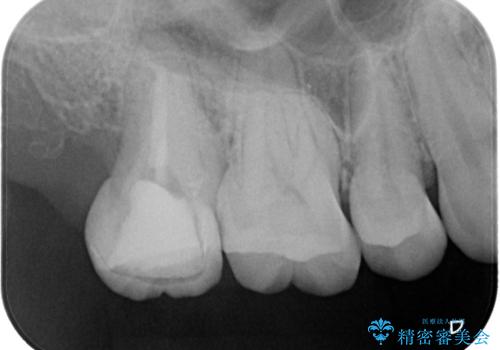

- 海外に転居する前に治療を完了させたいと来院された患者様です。

根管治療からセラミッククラウンまで来院回数は5回で治療を完了することができました。

治療前は遠心のポケットが7mmほどありましたが、治療後には3mmに改善しています。